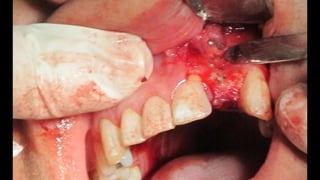

El documento trata sobre la cirugía bucal para plastía del proceso alveolar utilizando hueso humano y factores de crecimiento. También menciona los cuidados postoperatorios, que incluyen el uso de hielo, reposo, dieta líquida y antibióticos, evitando antiinflamatorios no esteroides. Se proporciona información adicional sobre las páginas web relacionadas con cirugía maxilofacial.